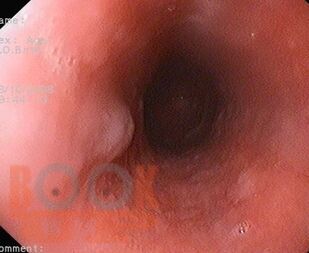

Монография содержит современные сведения об общих симптомах, связанных с желудочно-кишечными расстройствами при различных соматических заболеваниях. Освещены практические аспекты эндоскопической диагностики и лечебной тактики желудочно-кишечных симптомов при системных расстройствах (иммунологические, метаболические и эндокринные расстройства, пищевая аллергия и гиперчувствительность, беременность и гинекологические состояния) и различной патологии внутренних органов (кожные, сердечно-сосудистые, легочные, гематологические, неврологические, ревматологические заболевания, заболевания почек). Подробно изложены клиника желудочно-кишечных симптомов, их диагностика, эндоскопическая семиотика и лечение.

Монография предназначена для эндоскопистов, хирургов-эндоскопистов, гастроэнтерологов, терапевтов, врачей общей практики, а также предназначена для преподавателей медицинских вузов. Монография может быть использована как учебное пособие для студентов медицинских вузов, врачей-стажеров, клинических ординаторов, аспирантов, слушателей курсов повышения квалификации.